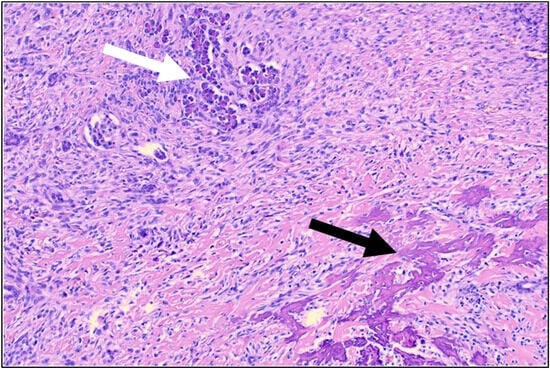

| 1 | 35 | m | osteoblastic (G3) | distal femur | CTx, OP, CTx (EURAMOS) | 129 | none | pancreas | single | 16 | yes | left pancreatectomy with splenectomy and gastric wedge resection | none | AWD | 8 |